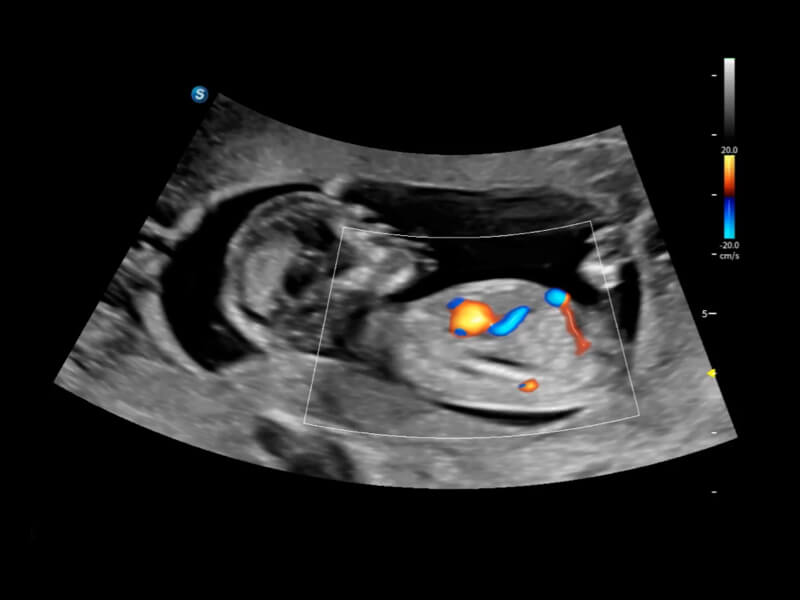

豐富的血流動(dòng)力學(xué)檢測(cè)技術(shù),可在不同醫(yī)療場(chǎng)景中高效捕捉血流信號(hào),助力臨床診療。

在傳統(tǒng)血流的基礎(chǔ)上優(yōu)化掃查和算法策略,能夠更好的抑制組織信息,提煉紅細(xì)胞運(yùn)動(dòng)信息,得到更高幀頻,高靈敏度和分辨率的血流信號(hào),還原更真實(shí)的血流動(dòng)力學(xué)。

通過(guò)光照模型,使二維血流顯示出立體的效果,增加血流的敏感性、成束性,減少外溢。可以和其他不同的血流技術(shù)聯(lián)合使用,融合不同技術(shù)的優(yōu)勢(shì)。輕松應(yīng)對(duì)微小血管,增強(qiáng)血流的立體效果,提升視覺(jué)敏感性。